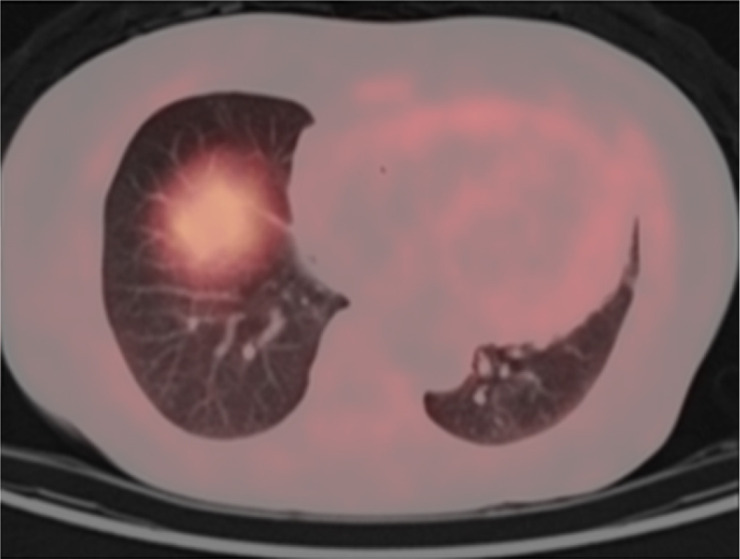

Abstract Image